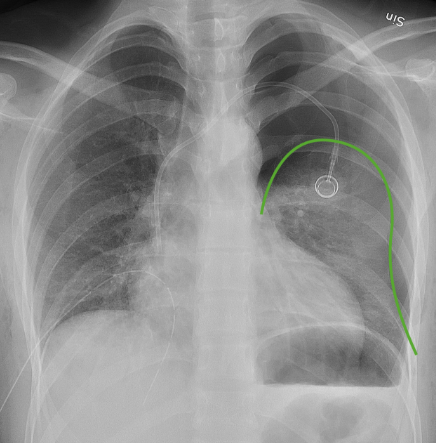

NEUMOTÓRAX. El neumotórax (a veces escrito erróneamente como neurotórax) es la presencia de aire en el espacio pleural, lo que provoca colapso parcial o total del pulmón del lado afectado. ¿CÓMO SE PRODUCE? El aire entra al espacio pleural por: Rotura alveolar...